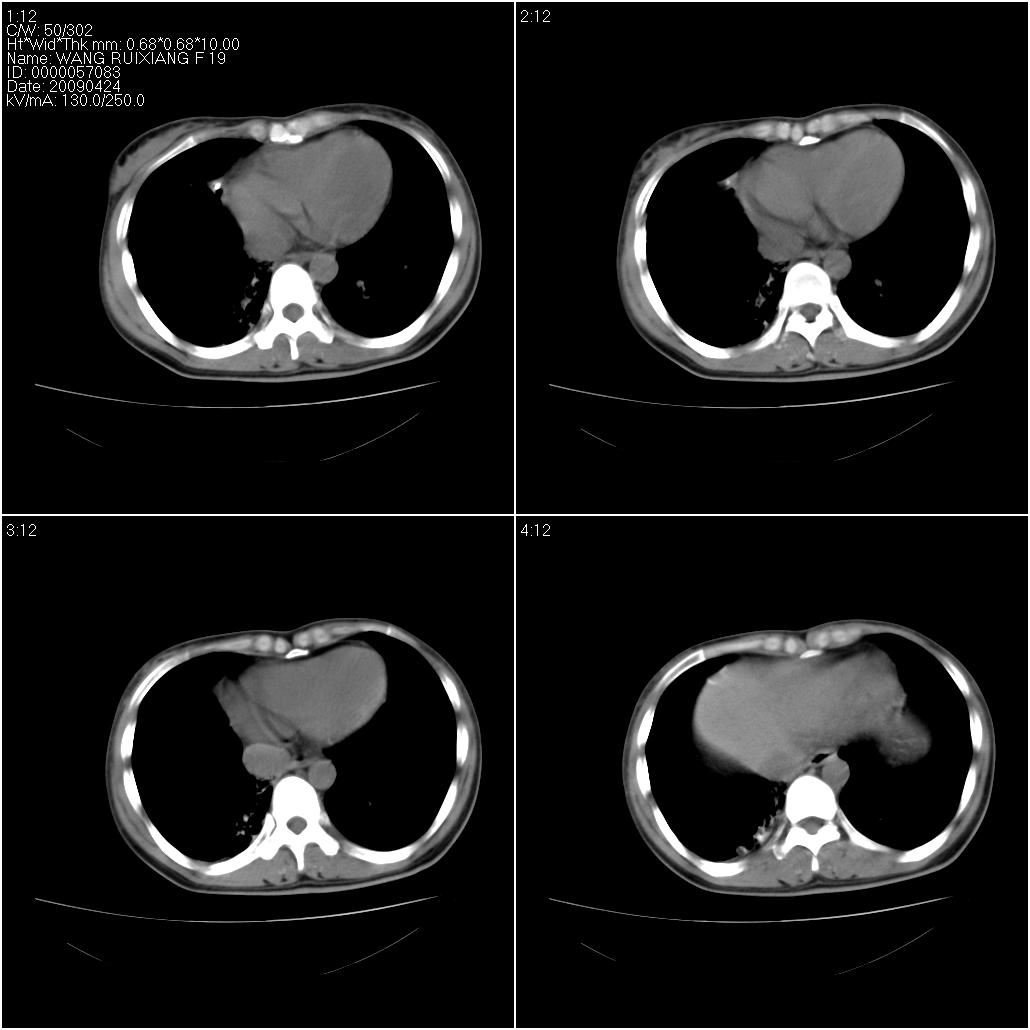

标题: CT19588:女性,39岁。患者胸闷不适,上楼时气喘。 [打印本页]

标题: CT19588:女性,39岁。患者胸闷不适,上楼时气喘。

片子上的年龄为19岁,是操作错误。该患者于去年5月份曾做平片和ct扫描,和这一次的ct检查没有明显变化。当时诊断为肺结核,进行抗痨治疗至今,但没有改善。呼吸功能试验为混合型呼吸困难。除此之外,该患者没有其他方面没有的临床症状和体征

两肺见斑点片状阴影,部分病灶密度较高,右下肺见小囊状及柱状蜂窝状阴形,考虑为两肺结核以阵旧性为主,右下肺支扩。

考虑肺淋巴管肌瘤病。

结合病人年龄(特别是生育期妇女)及临床表现多考虑淋巴管肌瘤病。